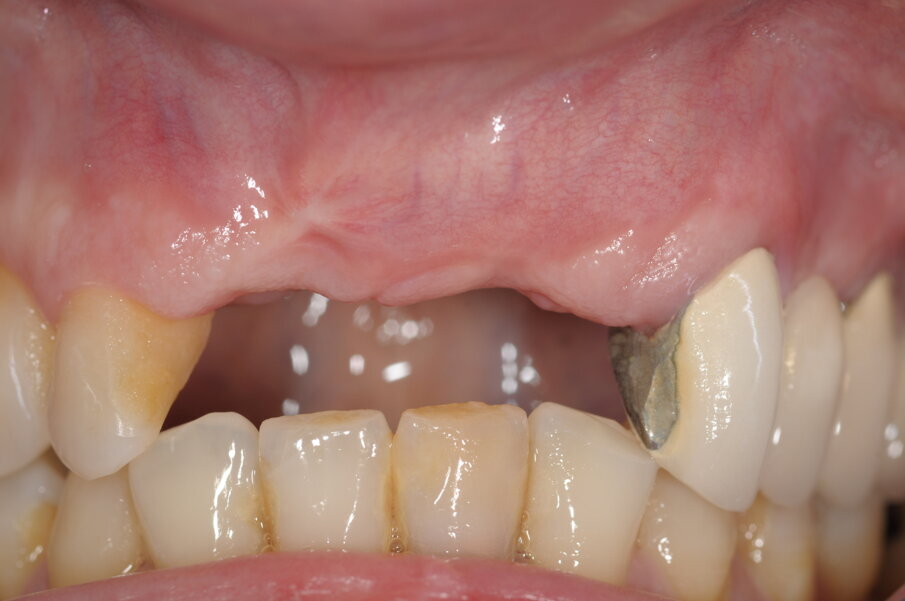

La paziente, donna, di anni 55, era giunta alla nostra osservazione richiedendo una riabilitazione protesica in area estetica a seguito di trauma provocato da un incidente stradale, avvenuto da circa 10 anni, che aveva determinando la perdita di due incisivi superiori in posizione 2.1, 2.2 (Figg. 1, 2).

La paziente ha categoricamente rifiutato queste soluzione di piano di trattamento, in particolare l’idea di un trattamento ortodontico e il rifacimento di precedenti restauri protesici. Richiedeva unicamente di trattare il settore frontale, esponendo gli operatori a un estremo e complicato compromesso. L’unico punto accettato è stato quello relativo alla necessaria estrazione dell’elemento 1.1 (molto compromesso dal punto di vista parodontale, preliminare alla tecnica di rigenerazione ossea) (Figg. 3, 4).

Fig. 2 - Visione frontale della zona edentula.

Fig. 5 - Situazione iniziale, visione occlusale..

Fig. 7 - Visione frontale dopo avulsione elemento 1.1.